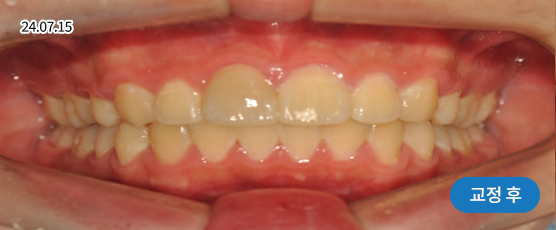

* 본 사진은 동일 조건에서 촬영되었으며, 환자 본인의 동의를 얻어 게재되었습니다.